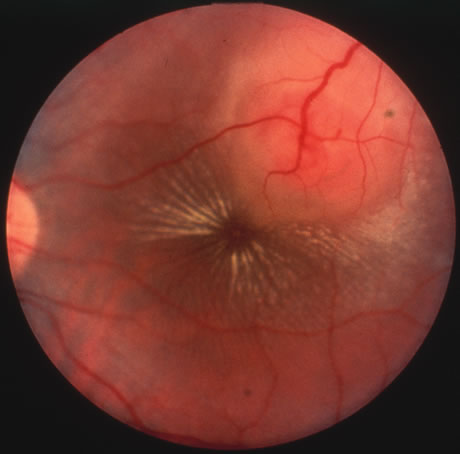

Rubella infections that occur early in gestation are associated with the greatest risk of fetal damage, however, infection in the third trimester may still cause damage. Maternal infection in the first 2 months of pregnancy results in a 40% to 60% chance of multiple congenital anomalies or fetal death. Congenital heart disease, cataracts, and deafness are the classic triad of the congenital rubella syndrome; however, there are many other commonly recognized complications of prenatal rubella infection (Fig. 13). Encephalitis, microcephaly, mental retardation, intrauterine growth retardation, thrombocytopenic purpura, hepatosplenomegaly, obstructive jaundice, interstitial pneumonitis, myocarditis, and radiolucent bone lesions are all possible sequelae of congenital rubella infection.54 The classic salt-and-pepper retinopathy occurs less commonly (Fig. 14), but may be noted to show progression. Other ocular findings include congenital cataracts, microphthalmia and glaucoma. Ocular disease and hearing loss frequently occur together, and glaucoma is frequently associated with microphthalmos.56

Fig. 13. A patient with the congenital rubella syndrome. Note the hearing aids, left esotropia, left microphthalmos and cataract.

Fig. 14. The classic salt-and-pepper fundus of congenital rubella.